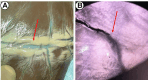

Results: After ICG injection into the individual coronary ostia, perfusion of the native coronary artery was visible. Portions of the vessels embedded into the epicardial fat could be easily visualized on the surface of the heart and the dissection facilitated via fluorescence guidance. The territorial distribution reflected the expected regional perfusion. The SVG graft was anastomosed to an OM branch. ICG visualization allowed for assessment of graft patency excluding potential technical anastomosis problems or graft twisting or dissection. The myocardial perfusion observed in real-time confirmed regional distribution to the entire lateral wall and minimally to the inferior wall. These findings were confirmed in all the specimens used in the study.